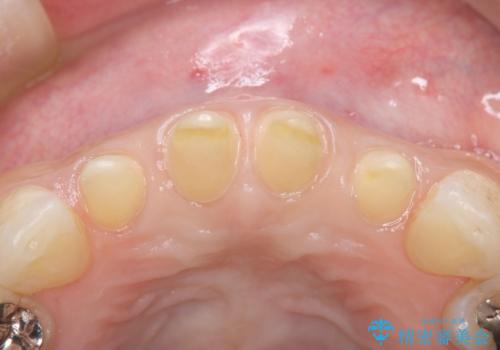

前歯の形気になる セラミッククラウン(SP)

- 矯正終了した患者様で、前歯の形が気になるということで

セラミッククラウンにて治療された方の症例です。

患者様と何度か修正を加えながら歯の形、色に満足していただけました。